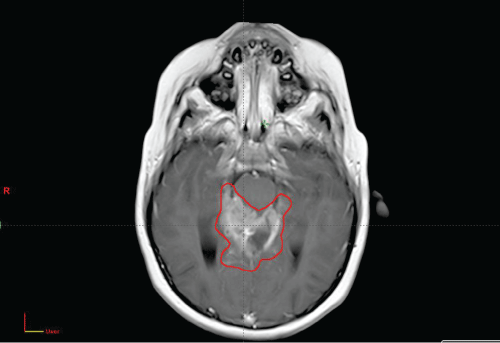

MRI Brain on Initial Presesentation with Gross Tumor Volume (GTV) Contoured for Radiation Planning.

image